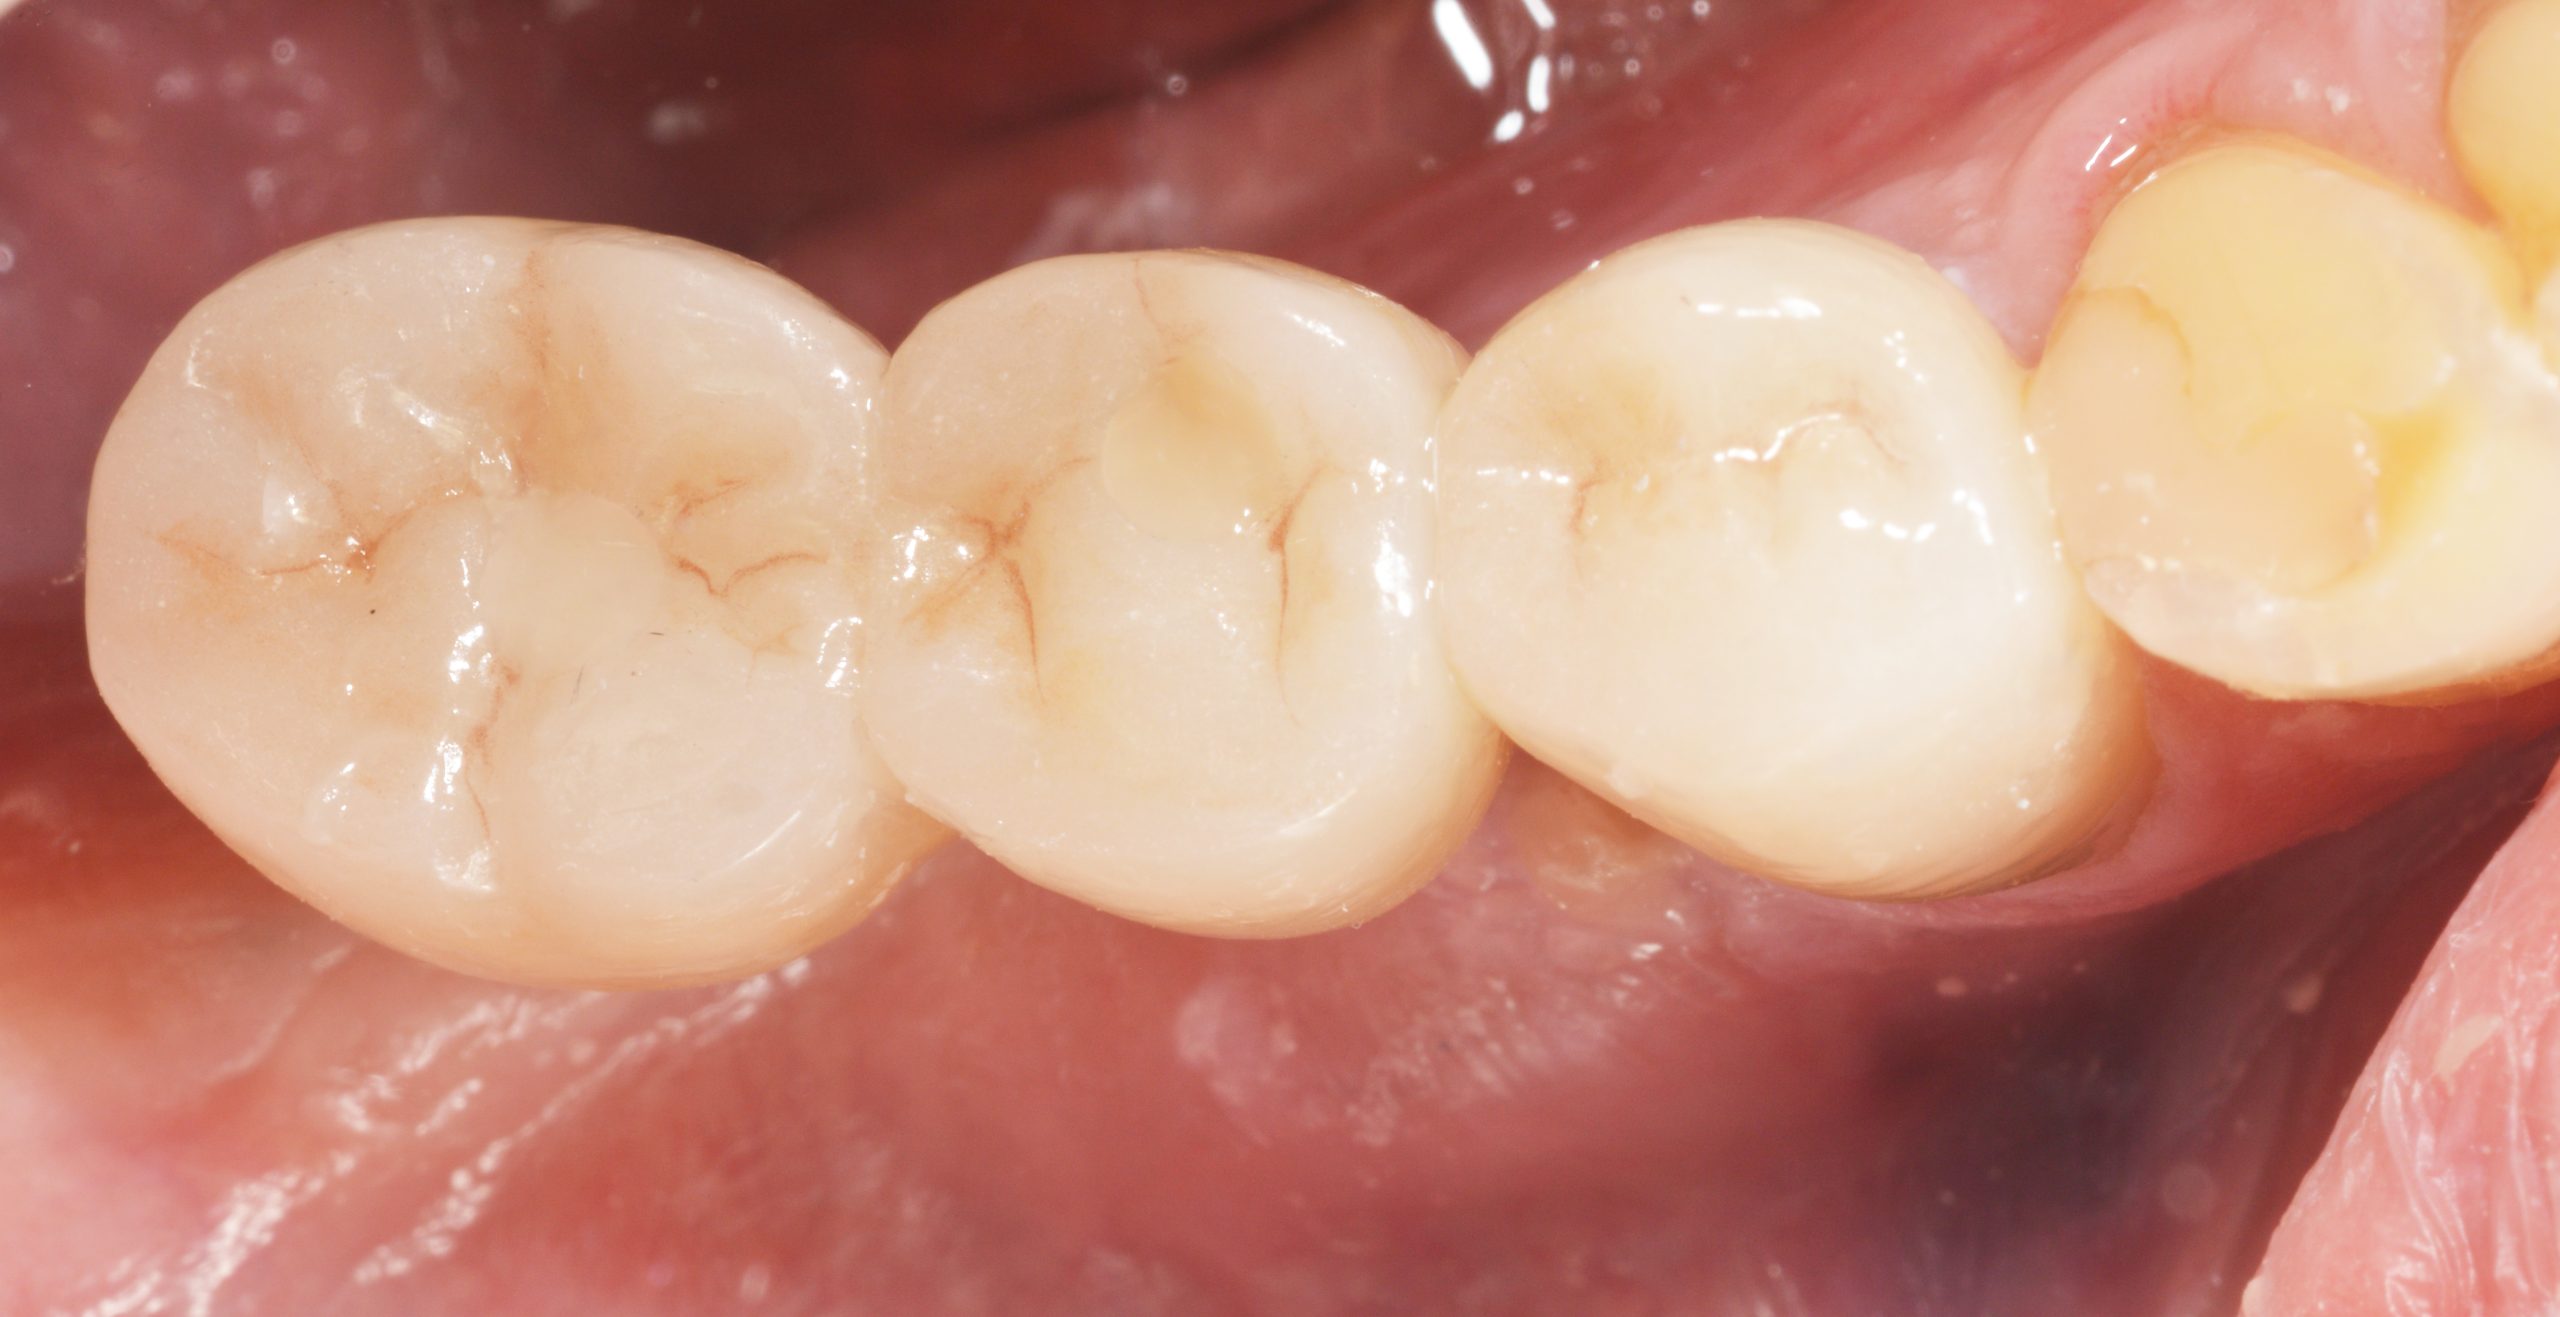

Nachdem die beiden Abutments angezogen und über den Schrauben aufgefüllt wurden, wurde der ZrO2-Block intraoral verklebt und die Öffnungen anschließend mit plastischem Material verschlossen.

Zusätzlich sorgte die Zahntechnik für einen reinigungsfreundlichen Durchgang basal zwischen 45 und 46. Die Handhabung der Interdentalbürsten wurde kontrolliert und der Patient mit entsprechenden Instruktionen in das regelmäßige Recall entlassen.